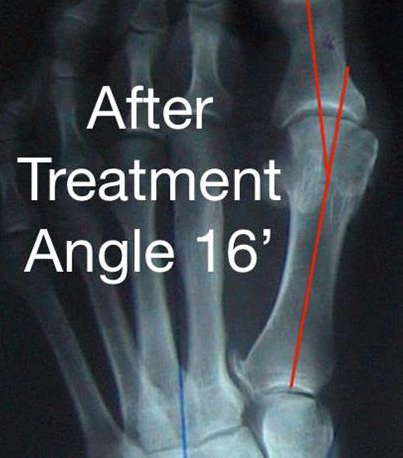

Many people think that surgery is the only treatment option for bunions. However, FMT is extremely successful in most cases. Using this method, we gently guide the joints back into the correct position and then strengthen the muscles around that joint to reinforce a new position. As a result, the body will naturally straighten the bunion, with help from the hands-on therapy that you receive in the clinic.